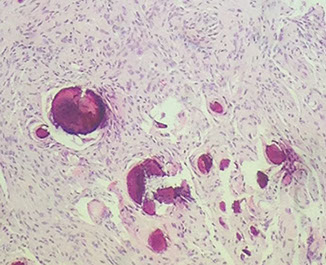

Cysticercosis

Pork tapeworm (Taenia solium) infx

- forms well-circumscribed cysts in brain, esp in intraventricular region

Can present c seizures, headache, sensory probs, dementia

Calcifications common

3 layers:

Undulating red waxy cuticle; germinal layer; inner loose myxoid layer